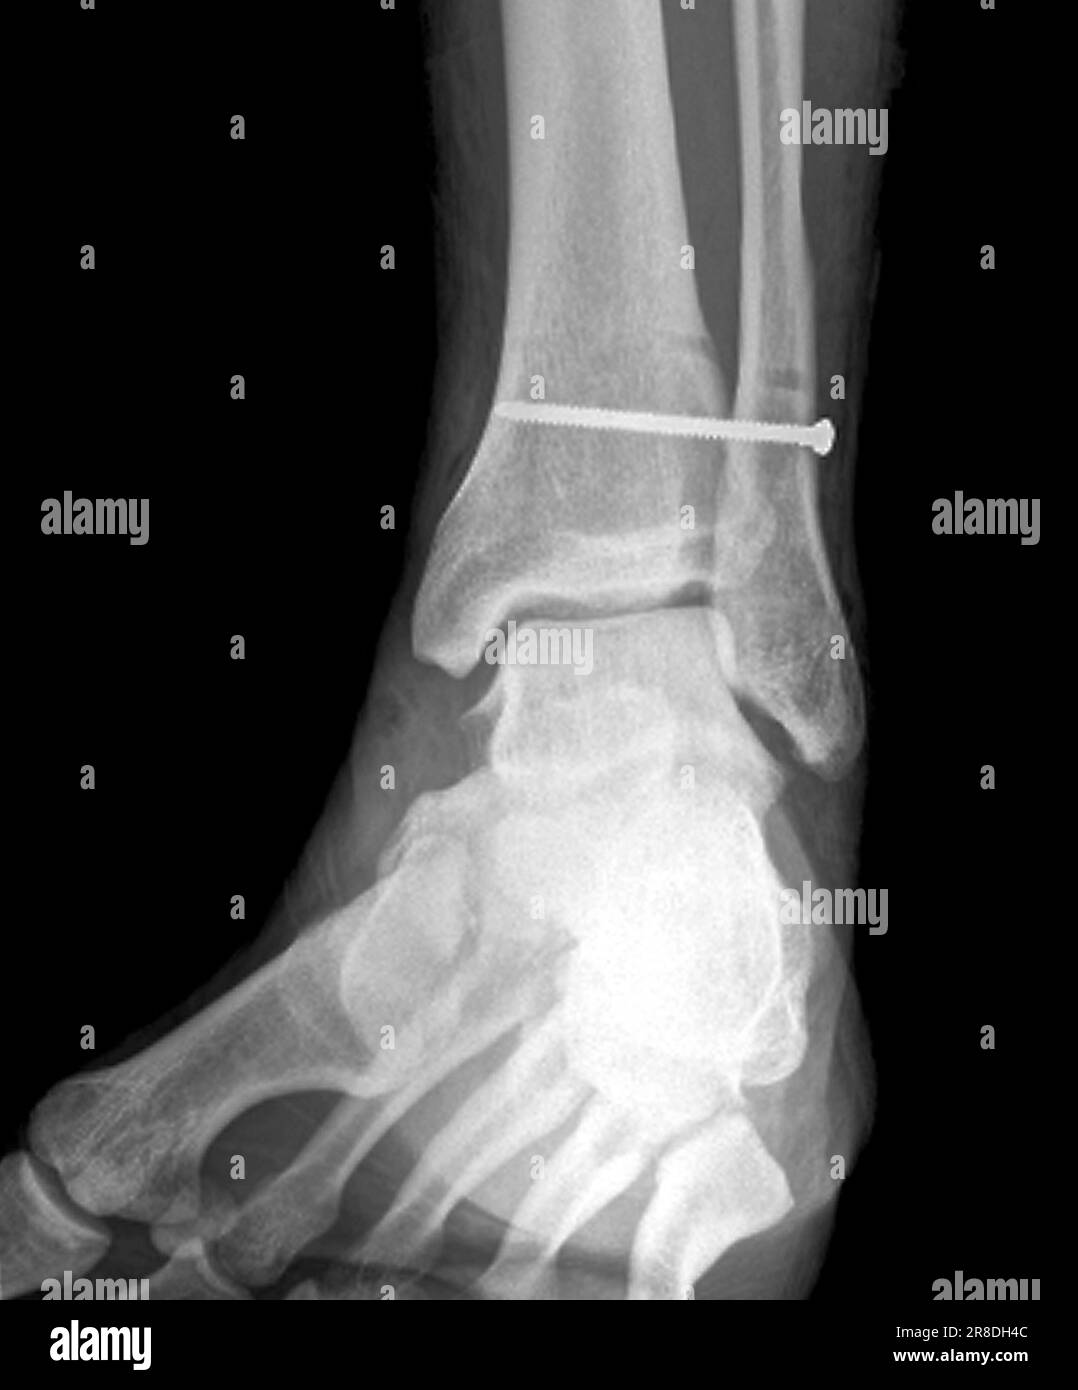

Coloured Xrays of the pinned ankle of a 32 year old male patient. A Calf In Bone Fracture A broken leg (leg fracture) is a break or crack in one of the bones in your leg. Fibula fractures occur around the ankle, knee, and middle of the leg. There are different types of fractures, which can also affect treatment and recovery. If you have a displaced fracture, the care. Common causes include falls, motor vehicle accidents. A broken. Calf In Bone Fracture.

Xrays of the pinned ankle of a 32 year old male patient. A screw is Calf In Bone Fracture What is a broken leg? There are three bones in your leg, including. Healthcare providers also call broken legs fractured legs. Common causes include falls, motor vehicle accidents. Here, health care providers typically evaluate the injury and immobilize the leg with a splint. A broken leg is a bone fracture (broken bone) in your leg. A broken leg (leg fracture). Calf In Bone Fracture.